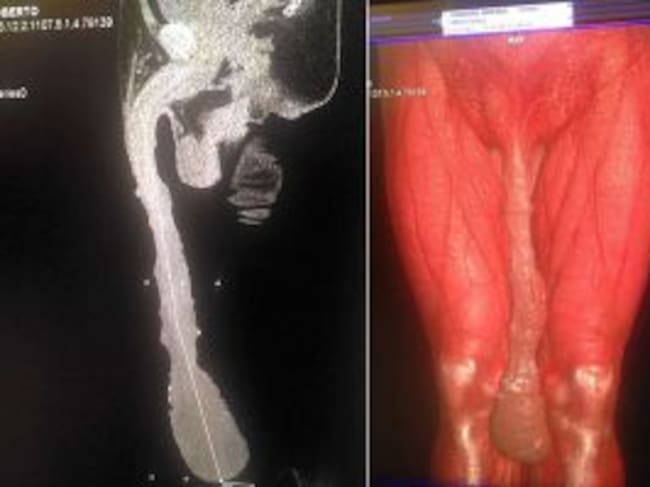

Roberto Esquivel Cabrera es un hombre común y corriente, con la única diferencia de que su pene ha alcanzado casi el medio metro de longitud, todo un récord.

El hombre superó con creces a otro que creía tener el miembro más largo: se trata del actor norteamericano Jonah Falcon, cuyo pene alcanzaba los 24 centímetros flácido y 34 centímetros erecto. El de Cabrera tiene 48 centímetros.